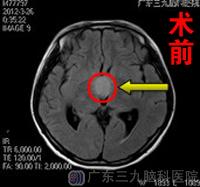

入院行头部CT检查见鞍上区及三脑室占位性病变,微侵袭神经外科吴杰主任结合其影像学检查及临床症状,初步诊断为颅咽管瘤,并为其制定了全面的手术治疗方案。入院第4天,在完善术前检查后小孔顺利接受了“鞍上区、三脑室内肿瘤切除术”,病理回报:颅咽管瘤。术后1周得以康复出院,目前已出院1年余,随访得知其月经已恢复规律。